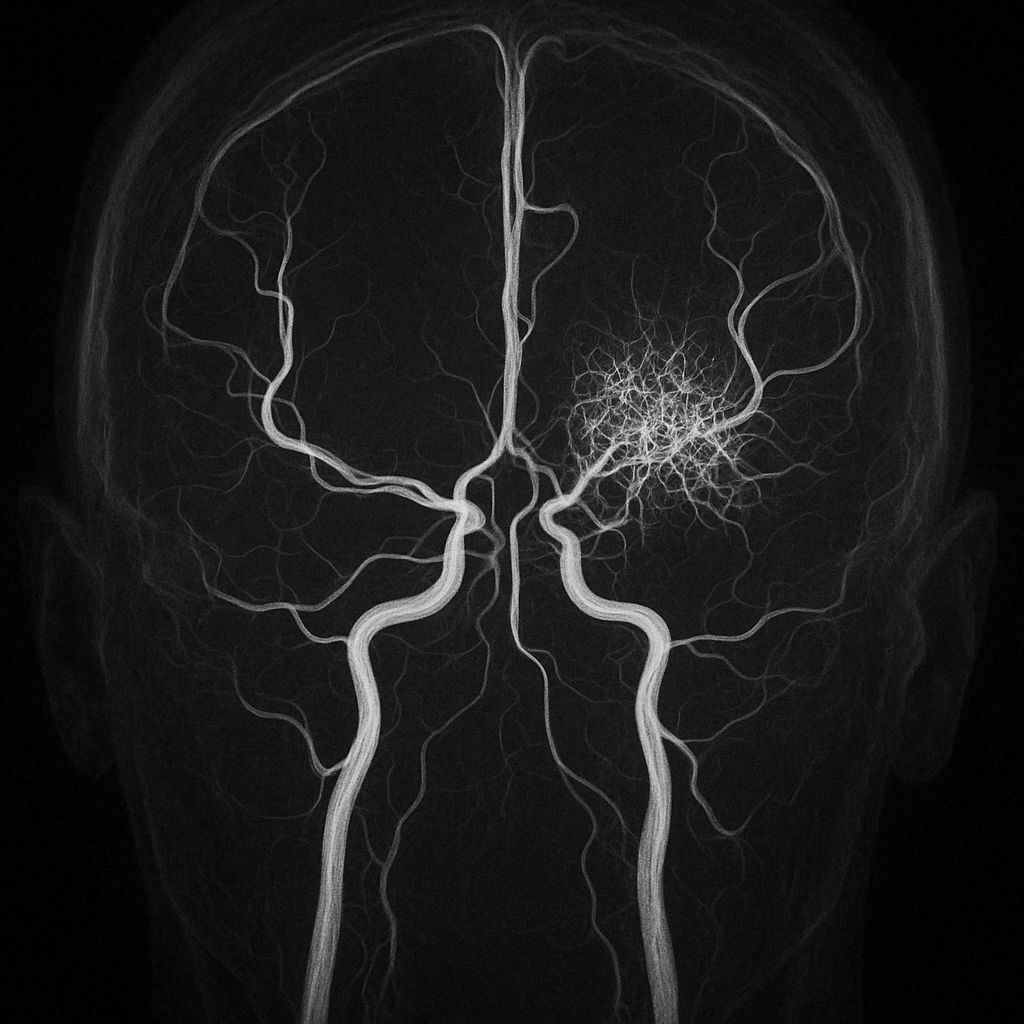

MRI of the spine may show gadolinium enhancement of nerve roots, particularly in the cauda equina.